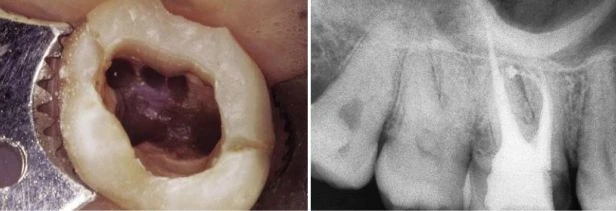

Cũng như răng cối lớn một dưới, răng này cũng thường cần điều trị nội nha. Nó cũng thường che đậy nhiều cạm bẫy và dẫn đến thất bại. Trong đa số các trường hợp, răng có ba chân với ba ống tủy độc lập nhau. Hiếm khi có hai chân với hai ống tủy (hình 11.53). Chân trong dài nhất và tròn theo mặt phẳng cắt ngang. Chân ngoài xa ngắn hơn một chút nhưng cũng hơi tròn theo mặt phẳng cắt ngang. Chân ngoài gần có thể dài hơn hoặc ngắn hơn nhưng dẹt hơn theo chiều gần xa.

Hình 11.53. A. Sàn tủy của răng #16 với hai miệng ống tủy, một ở trong và một ở ngoài. B. Phim sau điều trị: ống trong dài hơn và một ống ngoài, ống ngoài chia làm hai ống nhỏ hơn ở 1/3 chóp.

Hình 11.58. A. Phim trước điều trị của răng #16 với năm ống tủy. B. Xoang tủy bộc lộ năm miệng ống tủy sau khi năm ống này đã được làm sạch và tạo hình. C. Đưa năm cây dụng cụ vào năm ống tủy (đưa năm dụng cụ vào chỉ để lấy ảnh làm tư liệu chứ không phải là đo chiều dài năm ống cùng lúc). D. Phim trong lúc điều trị. E. Hình ảnh các ống tủy chụm lại ở vùng chóp. Các ống tủy dường như không có những lỗ chóp riêng biệt. F. Phim sau điều trị.

Trong ba chân, chân ngoài gần có nhiều hình dạng giải phẫu nhất. Nó hoàn toàn dẹt theo chiều gần xa. Vì vậy ống tủy chân răng có hình dạng như dải băng, hoặc thường có hai ống tủy phân biệt. Tỉ lệ % có hai ống tủy theo mỗi tác giả khác nhau cũng khác nhau, nhưng tất cả đều nhất trí rằng: tỉ lệ này >50% [ 53% theo Hess, 60.7% theo Pineda và Kuttler, 64% theo Smith và Nosonowitz và Brenner, 69.4% theo Acosta Vigouroux và Trugeda Bosaans, 84% theo Aydosand Milano, 93% theo Stropko và 96,1% theo Kulid (Bảng I)]

Nghiên cứu gần đây của John Stropko rất thú vị, ông cho rằng ống tủy thứ hai của chân ngoài gần tồn tại ở nghiên cứu “in vivo” trong 93% trường hợp và có thể đánh giá được lỗ chóp của nó trong 90% trường hợp. Stropko, trong một bài báo của ông, có viết rằng tỉ lệ % ông tìm thấy cao như vậy là nhờ ứng dụng kính hiển vi phẫu thuật và trong một vài trường hợp rất khó, có thể nói rằng không thể quan sát được miệng MB2 nếu không dùng kính hiển vi phẫu thuật. Một điều thú vị rằng là sử dụng kính hiển vi phẫu thuật nghiên cứu thì tỉ lệ % hiện diện MB2 cao hơn khi nghiên cứu mà sử dụng những phương tiện khác. Miệng của ống MB2 – nên gọi tên là ống tủy gần trong – nằm trong rãnh nối giữa ống trong và ống gần ngoài (hình 11.59 A, B). Để tìm MB2 ta có thể tìm một chỗ lõm nhỏ trên rãnh nói trên, tại điểm này cây thám trâm nội nha bị giữ lại. Tuy nhiên đôi lúc thám trâm không đi vào được vì thành gần của buồng tủy tạo một góc rất nhọn với sàn tủy và cản trở tầm nhìn, cũng như là thám trâm không chạm được vào miệng ống tủy (hình 11.59 C). Thành gần của buồng tuỷ có một gờ ngà che đi miệng của MB2 nằm bên dưới nó (hình 60A). Vì góc này, MB2 rất khó đánh giá. Trong 1-3mm đầu, ống tủy nghiêng 1 góc nhọn về phía gần, đây là lý do vì sao đầu trâm không thể tiến về phía chóp hơn một vài mm và nó bị dừng lại tại thành gần. Vì vậy trước khi tiến hành đánh giá ống tủy này cần mở góc này đi để loại bỏ gờ ngà trên thành gần xoang tủy, tạo một đường vào thẳng đến ống tủy. Điều này có thể thực hiện được dễ dàng, an toàn và hiều quả bằng máy siêu âm, chẳng hạn với đầu CPR và ProUltra (hình 11.60B). Nếu nhà lâm sàng loại bỏ gờ này bằng trâm thay vì dùng máy siêu âm thì hình dạng miệng MB2 sẽ như trong hình 11.59D.

Hình 11.59. A. Xoang tủy của răng cối lớn thứ nhất hàm trên. Chú ý rãnh chạy bắt đầu từ miệng ống gần ngoài hướng về ống trong. B. Rãnh này sau khi làm sạch và tạo hình ống gần trong. Chỗ lõm phía xa cũng được mở bởi một mũi khoan tròn nhỏ vì nghi ngờ có ống xa trong. C, D. Hình vẽ cho thấy góc giữa sàn tủy và gờ ngà ở thành gần xoang tủy (Courtesy of Dr. S. Buchanan). E. Hình dạng miệng ống tủy gần trong nếu gờ ngà không được loại bỏ bằng máy siêu âm.

Hình 11.60. A. Ảnh chụp với độ phóng đại 12 lần bộc lộ miệng của ống gần ngoài và rãnh liên quan. Một gờ ngà che đi miệng ống tủy bên dưới. B. Sau khi mở một đường vào thẳng, dùng đầu siêu âm thích hợp loại trừ gờ ngà một cách dễ dàng và an toàn, bộc lộ miệng ống tủy gần trong (Courtesy of Dr. C.J. Ruddle)